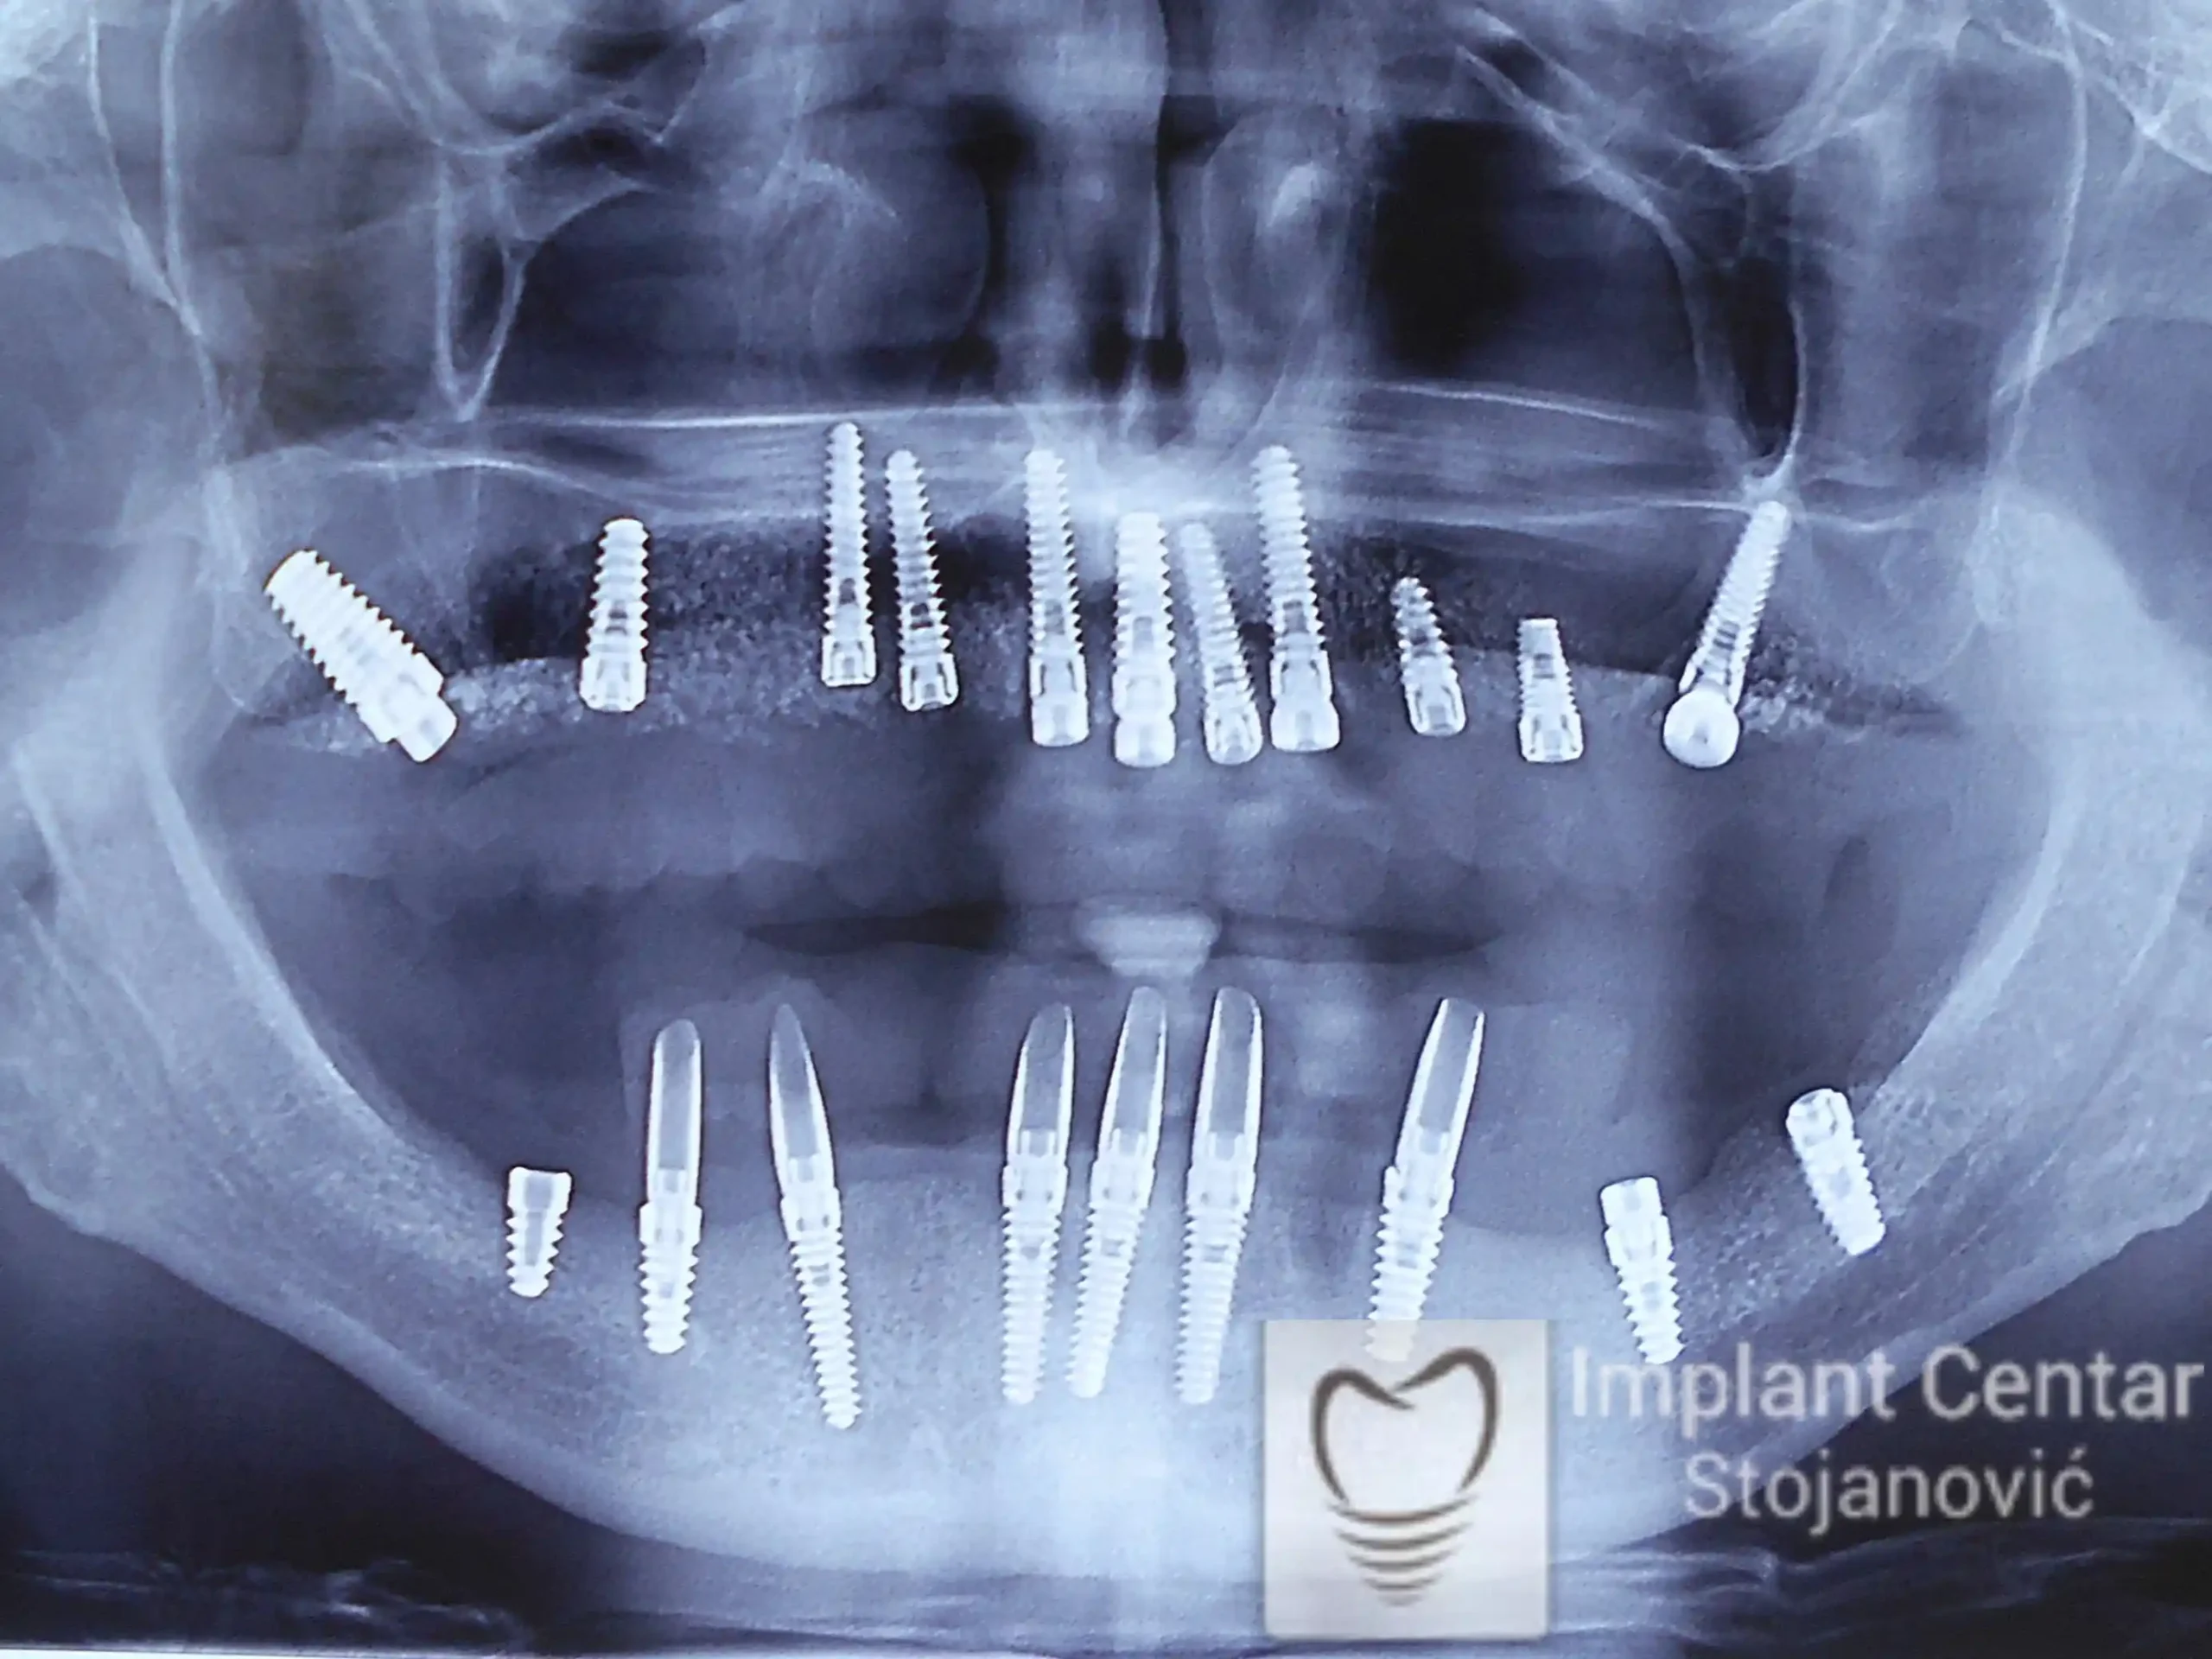

Na slici 1. i slici 2. prikazan je izgled pacijenta pre početka terapije – klinički i rendgenološki.

Nakon vađenja zuba, ugrađeni su implantati. Na slici 3 prikazan je ortopan snimak sa ugrđenim implantatima. Tokom perioda osteointegracije, pacijent je bio zbrinut fiksnim privremenim krunicama na implantatima, koje su izrađene samo dva dana nakon hirurške intervencije.

Na slikama 5. i 6. prikazan je izgled definitivnih cirkonijum-keramičkih mostova na implantatima.